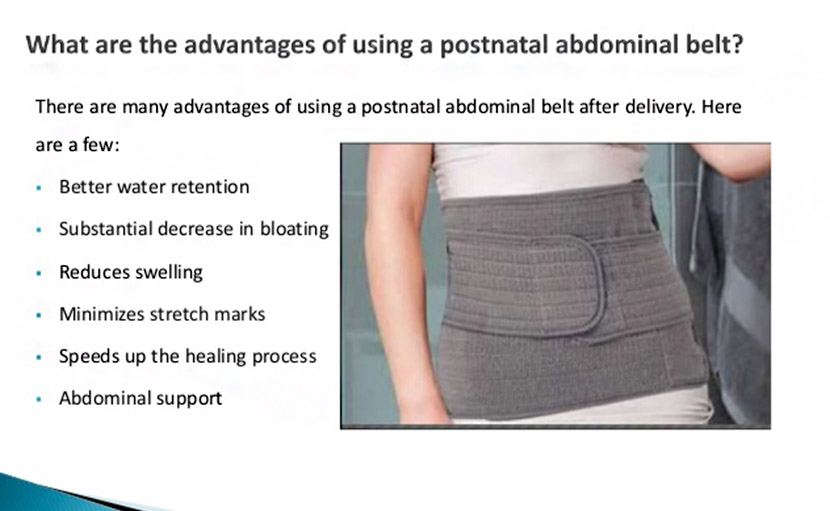

সিজারের পর বেল্ট ব্যবহার মেদ কমাতে কতটা কার্যকরী?

0 SHARES Share Tweet সন্তান জন্ম দেয়া একজন নারীর জীবনের অনেক কঠিন সময়। গর্ভবতী মায়ের সন্তান গর্ভে থাকাকালীন যেমন তার যত্...